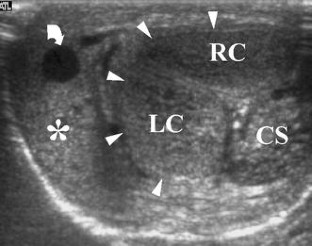

Fig. 1